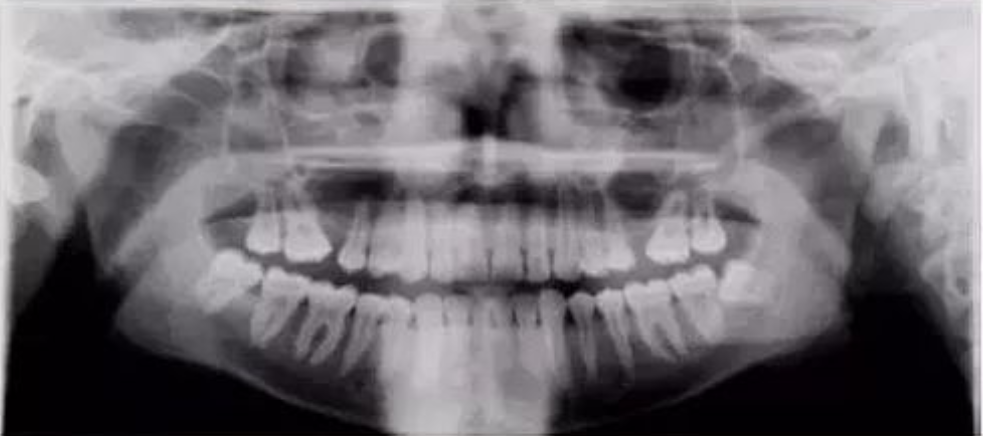

九、两侧下颌支与牙齿大小不同

【失误原因】

患者扭动。

【解决方法】

确保患者在全景成像时候处于直立稳定状态。